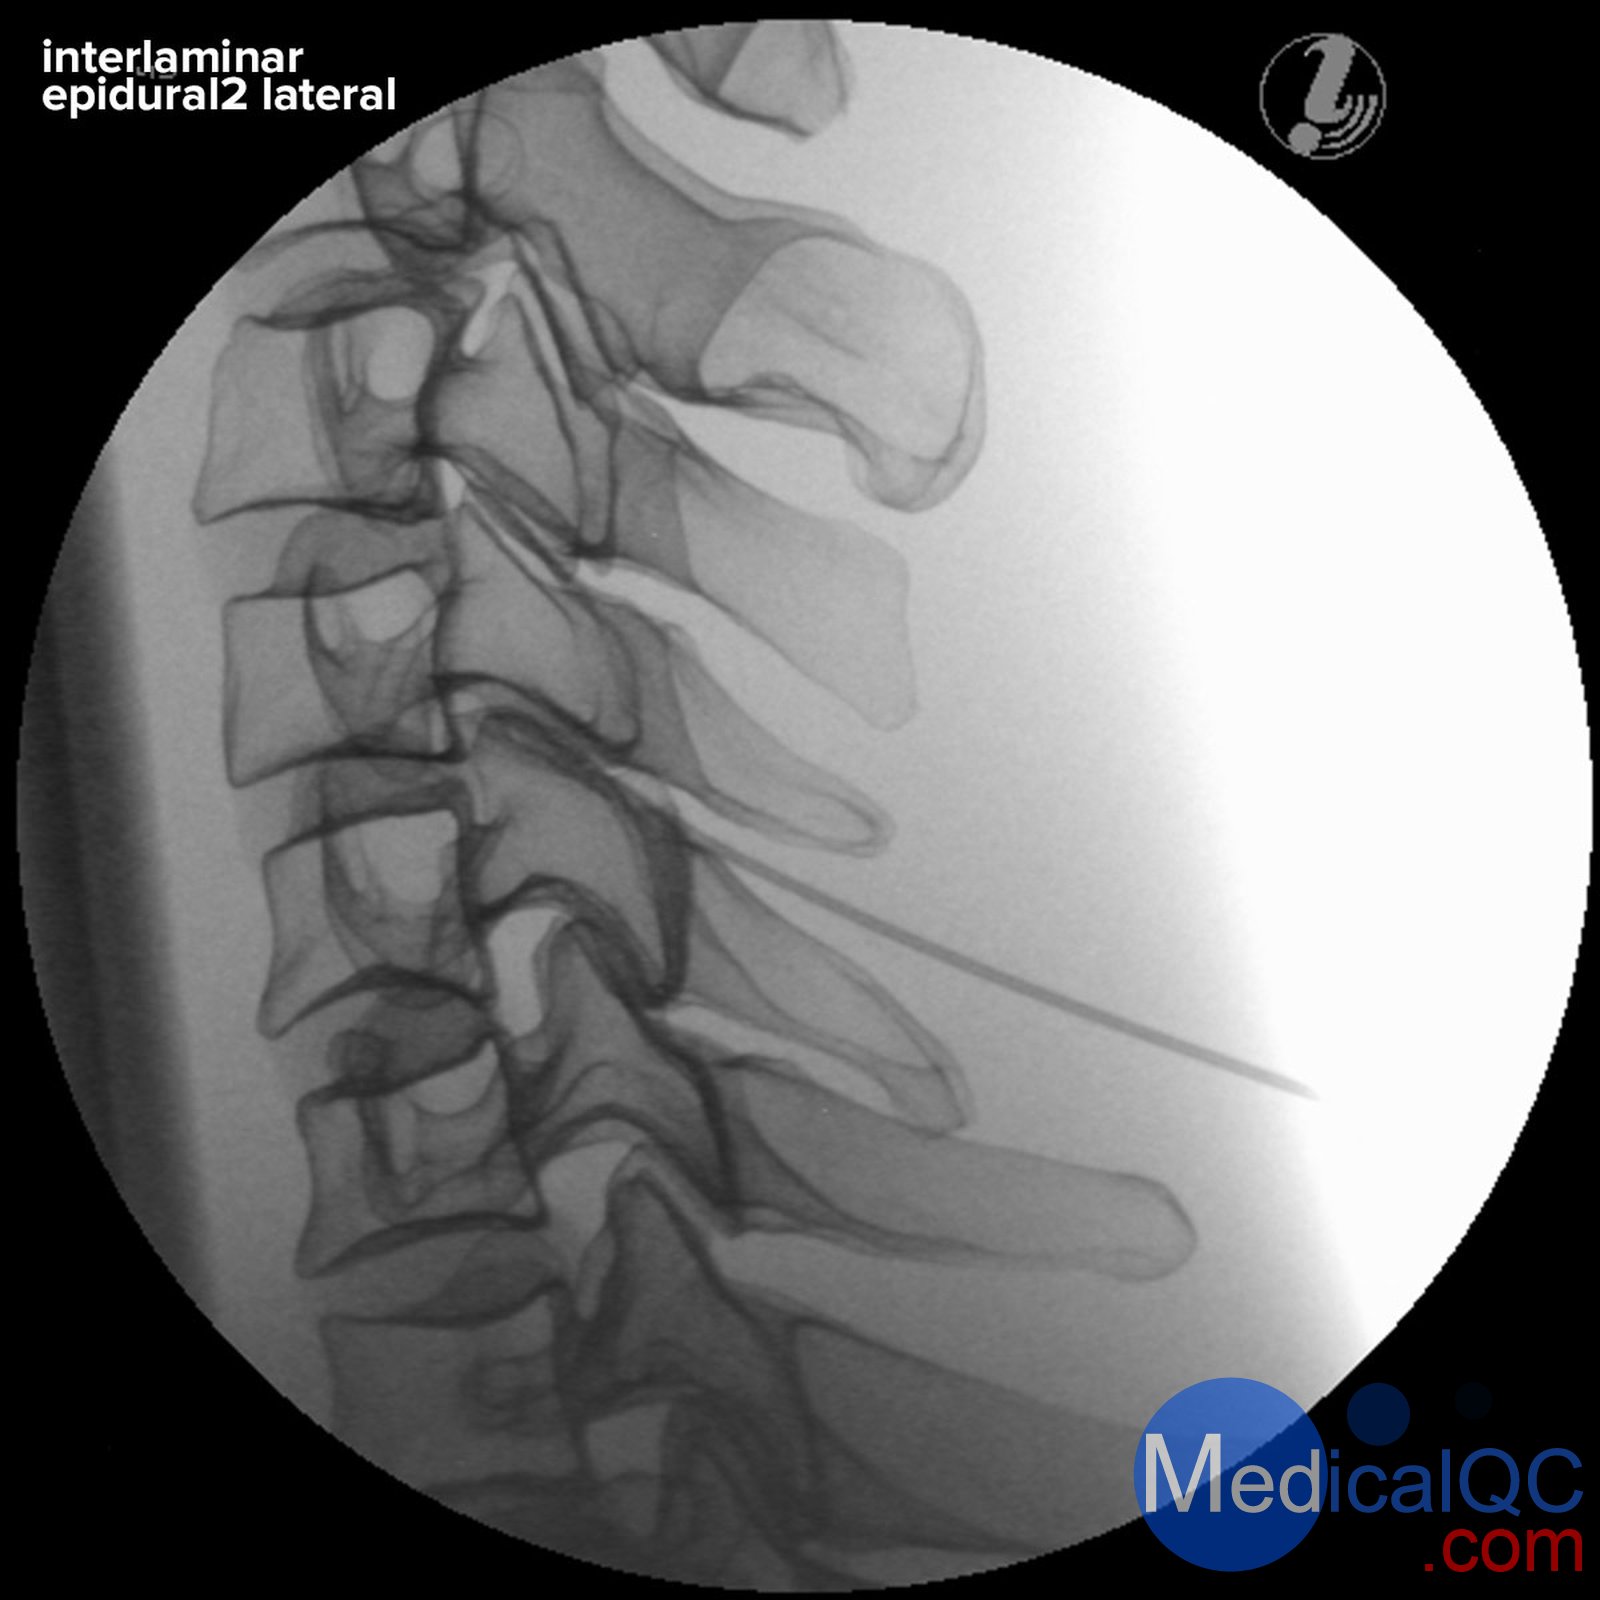

3B P67頸椎圖像引導(dǎo)穿刺訓(xùn)練模體,3B P67頸椎穿刺訓(xùn)練模體支持圖像的頸椎注射訓(xùn)練器

3B P67頸椎圖像引導(dǎo)穿刺訓(xùn)練模體,3B P67頸椎穿刺訓(xùn)練模體對(duì)頸椎栩栩如生的射線不透逼真的圖像引導(dǎo)下注射訓(xùn)練

圖像引導(dǎo)宮頸注射教練讓學(xué)員開發(fā)成功的脊柱手術(shù)過程的立體的認(rèn)識(shí)。他們將學(xué)習(xí)如何通過成像和解剖學(xué)檢查將成像與頸椎解剖結(jié)構(gòu)相關(guān)聯(lián),以識(shí)別目標(biāo)組織和脆弱結(jié)構(gòu),并應(yīng)用最佳實(shí)踐以確?;颊咴诩怪中g(shù)期間的安全性。

Interlaminar硬膜外注射